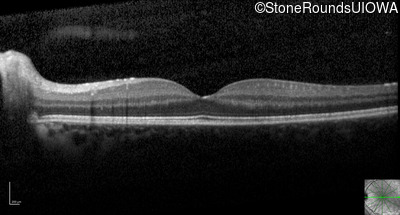

Optical Coherence Tomography - Right - 20/25 -2

Exemplar / OCT Stack